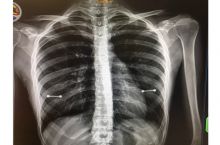

Hope all of you vaxxers have a great day!